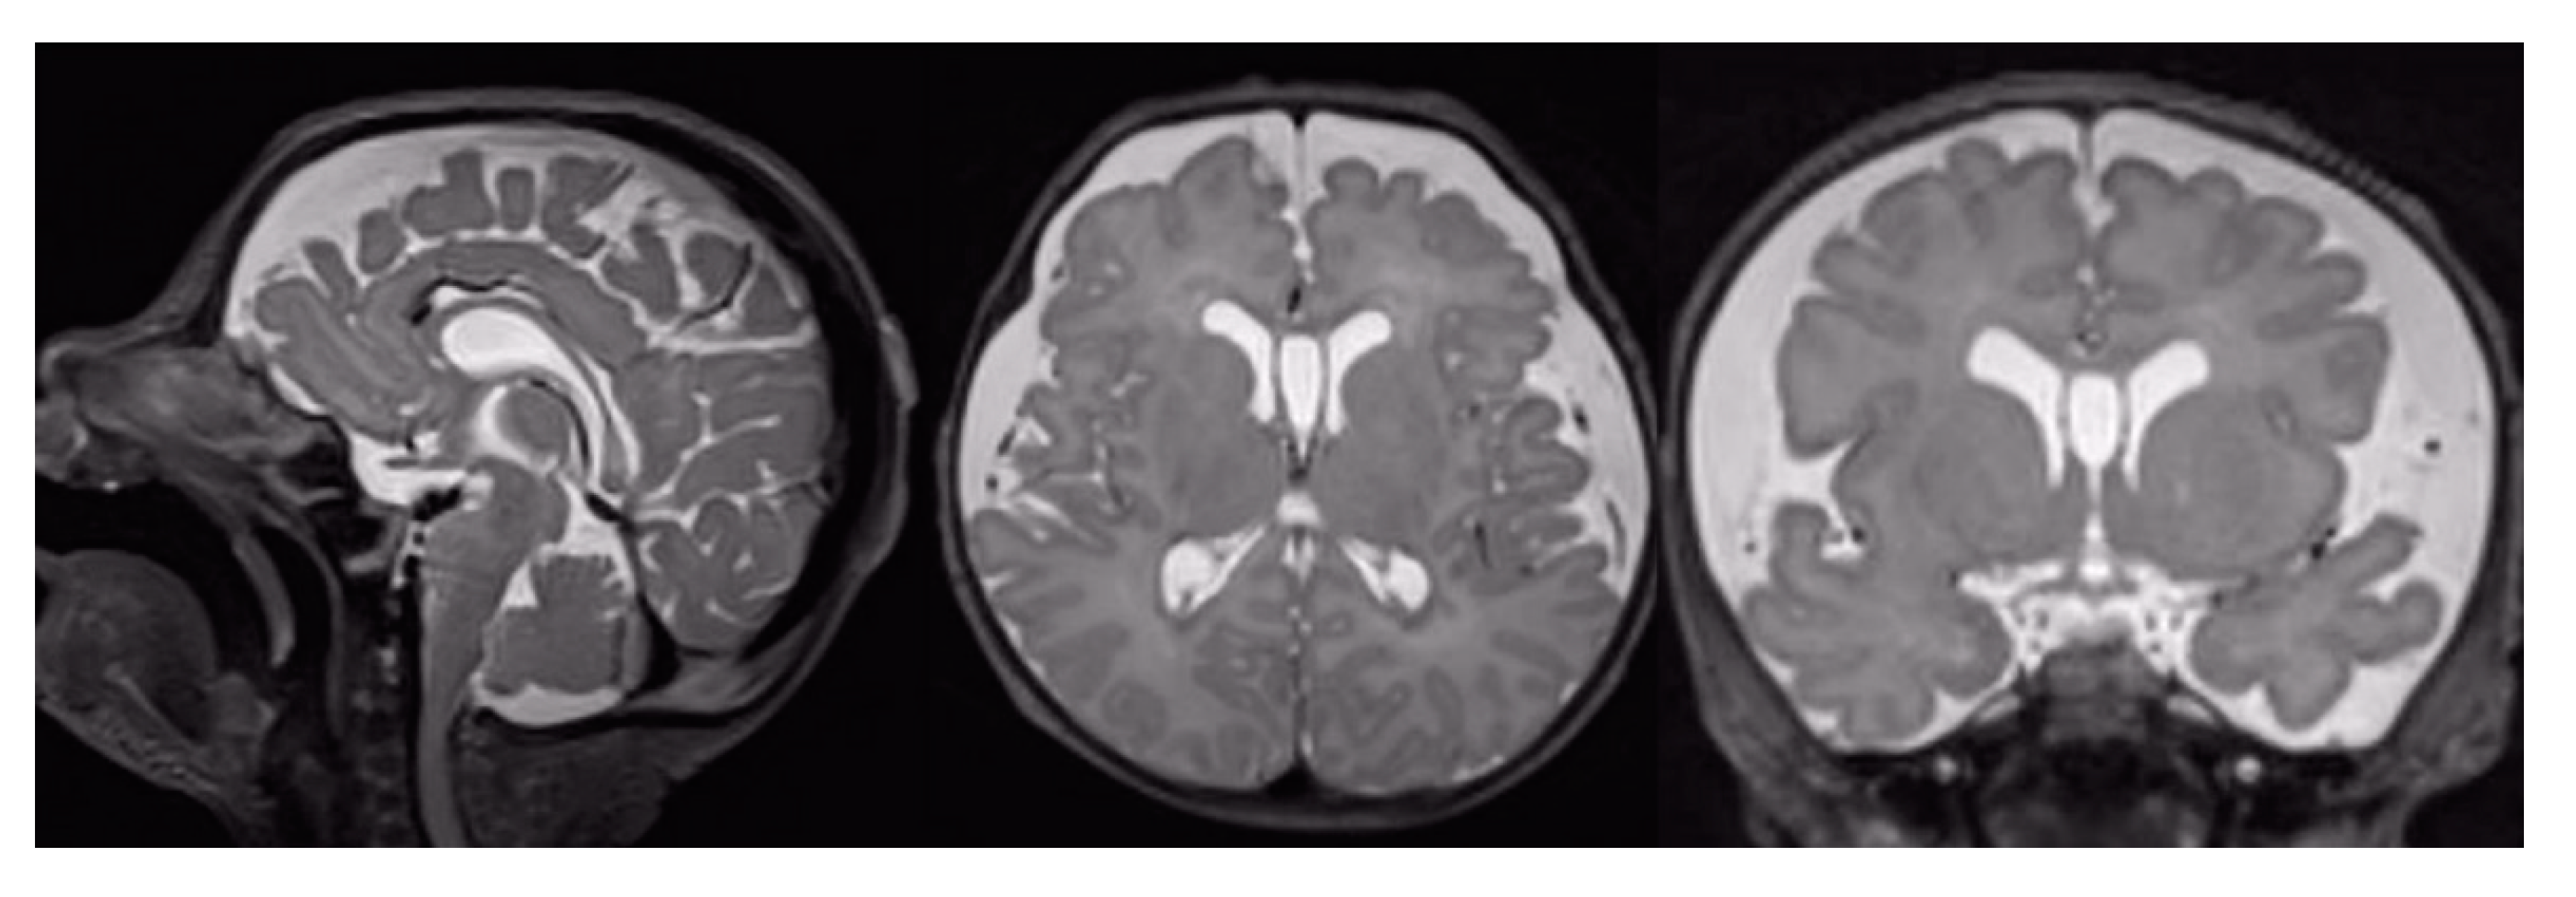

The evaluation of conventional MR images demonstrated the presence of positive findings (damage score greater than 0) in 10/16 patients (62.5%). In particular, the following were documented: ventriculomegaly in 4 patients (24.8%), increased subarachnoid spaces (SAS) in 6 patients (37.5%), intraventricular haemorrhage in 3 patients (18.7%), intraparenchymal haemorrhage in 3 patients (18.7%), cerebellar haemorrhage in 1 patient (6.2%), WM damage in 1 patient (6.2%), GM damage in 1 patient (6.2%), basal ganglia damage in 2 patients (12.5%) The increase of the SAS (Figure 1) was the most frequently found finding in the sample of our patients (Table 4).

Figure 1.

T2-weighted MRI of a CDH patient. Sagittal, axial and coronal view of the brain shows an enlargement of the SAS in the fronto-insular region bilaterally.